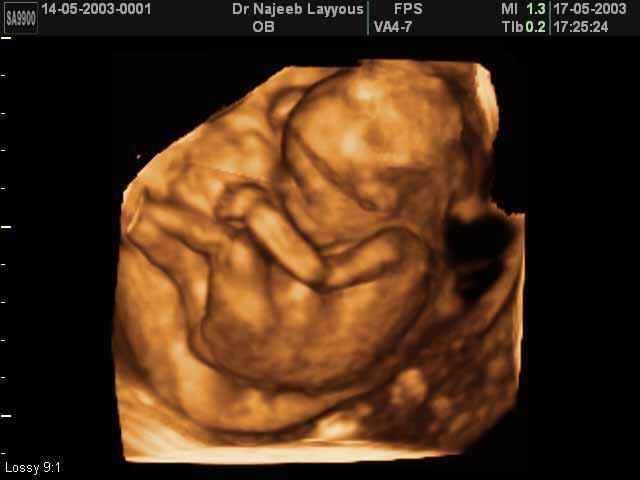

3D second trimestre échographie Photos de numérisation - deuxième partie de la grossesse